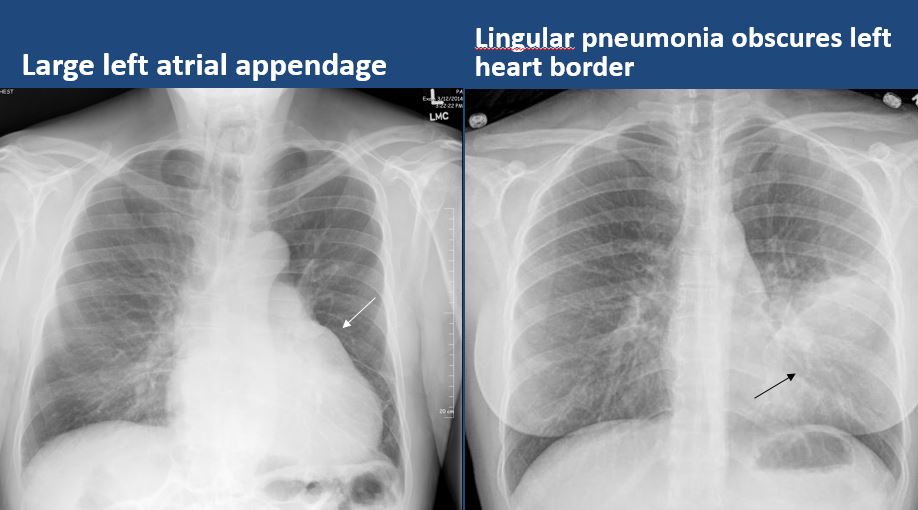

The heart borders are abnormal. [Yes/No]

The right or left hemidiaphragm is focally or diffusely obscured. [Yes/No]